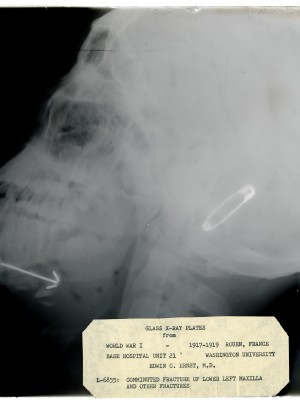

Ernst, Edwin Collection

Dr. Edwin Ernst, an only child born to St. Louis residents Charles and Catherine Ernst, was a notable Roentgenologist, a physician who specializes in radiological work. Dr. Ernst studied at Washington University in St. Louis and later at Moravian College in Bethlehem, Pennsylvania earning his advanced degrees. For two years he served as a resident physician at the St. Louis Mullanphy Hospital before leaving to pursue a private practice. When the United States formally entered the war in 1917, Ernst left St. Louis to become chief radiologist at Base Hospital 21. He was discharged honorably in 1919 with the citation of Major. His collection consist of x-ray images taken at Base Hospital 21 as well as drawings of radiological equipment and photographs.